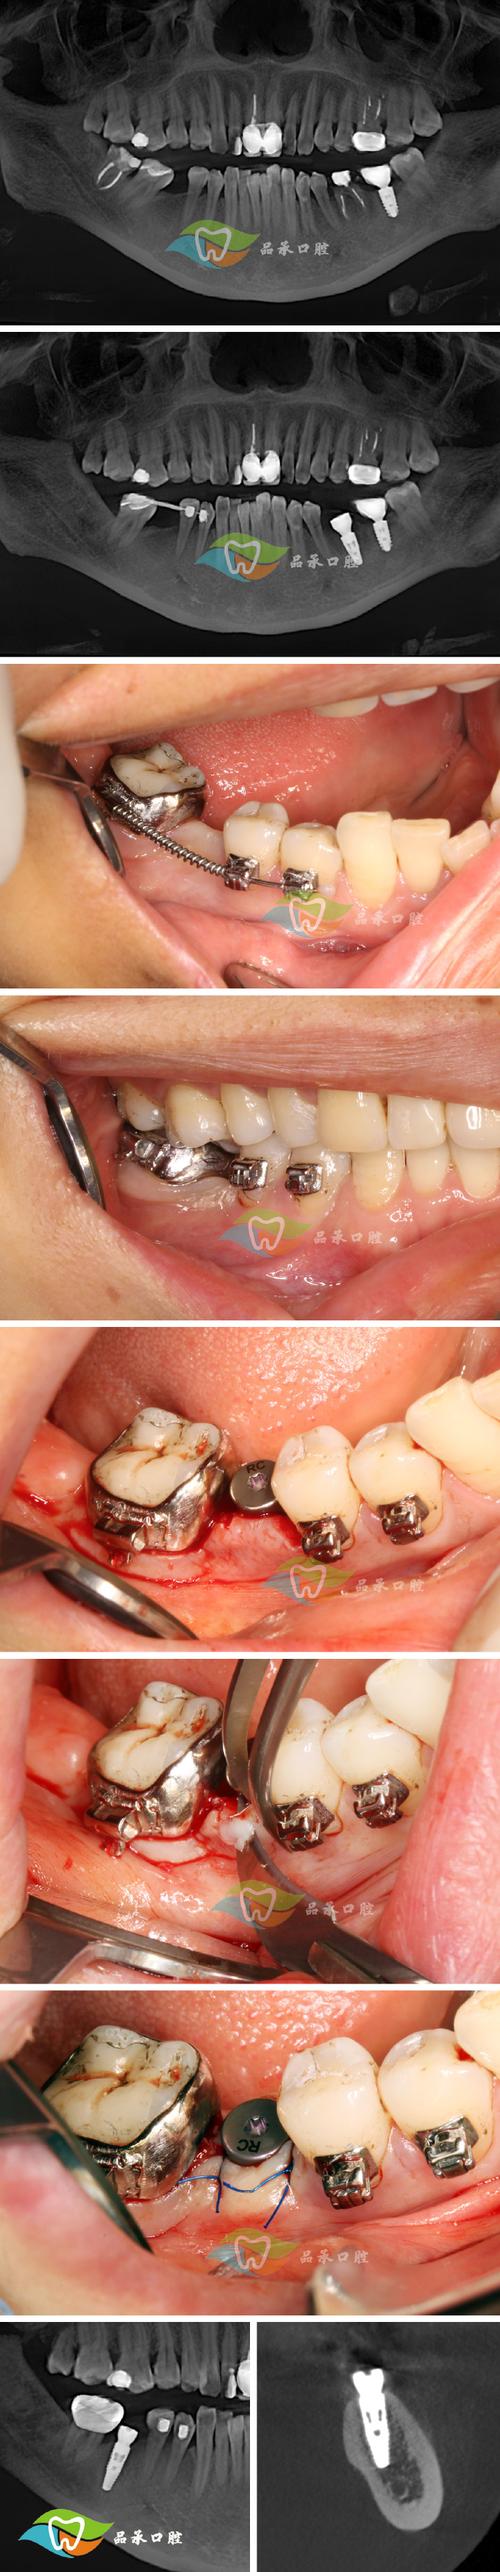

案例1:上班族小张,前牙外伤断裂(28岁,程序员)

问题:加班回家时不小心撞到桌角,门牙断裂至牙根,牙龈出血剧烈,影响美观和进食。

过程:

- 2小时内赶到拜博口腔,CBCT显示牙根未折断,但牙髓暴露,无法保留;

- 当天完成“微创拔牙”,并在新鲜牙槽窝内植入亲水性种植体;

- 安装临时树脂牙冠,当天即可正常说话,1周后恢复工作;

- 3个月后更换全瓷永久牙冠,颜色与邻牙一致,看不出“种植痕迹”。

小张反馈:“本来以为要请假几个月,结果拜博帮我一天搞定,现在啃苹果、吃排骨都没问题!”